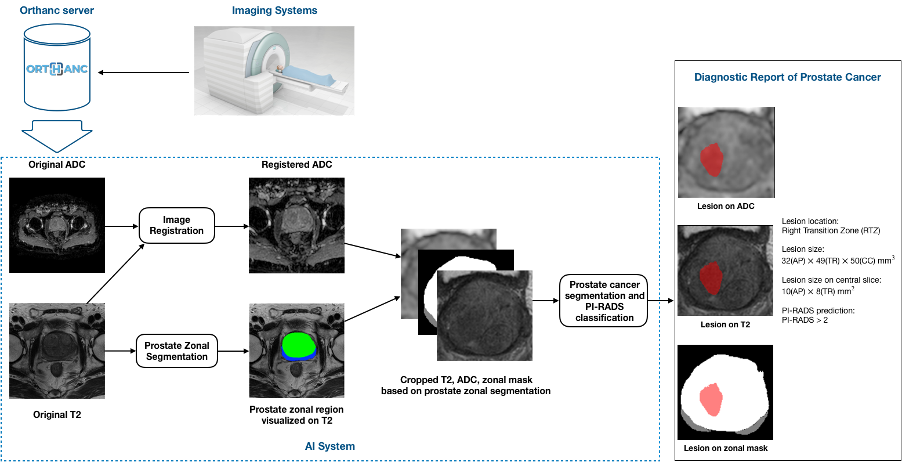

MRI is the primary imaging approach for diagnosing prostate cancer. Prostate Imaging Reporting and Data System (PI-RADS) on multiparametric MRI (mpMRI) provides fundamental MRI interpretation guidelines but suffers from inter-reader variability1. Deep learning networks show great promise in automatic lesion segmentation and classification, which help to ease the burden on radiologists and reduce inter-reader variability. Recent studies have shown the feasibility of detecting prostate cancer on mpMRI, using deep neural networks2,3,4,5. However, few considered the relative spatial information of prostate cancer to different anatomical structures to help identify prostate cancer from other anatomical tissues. Also, most of them require a large amount of annotated data which is costly and difficult to acquire in practice. Capsule Network (CapsNet)6 helps mitigate data starvation in deep learning-based medical image analysis due to its promising equivariance properties, representing the spatial/viewpoint variability of an object in a capsule (i.e., vector) format7. In this study, we proposed a pipeline including a novel multi-task network, MiniSegCaps, for prostate cancer segmentation and PI-RADS classification on mpMRI in an end-to-end manner and a graphical user interface (GUI) for diagnosis reports generation (Fig. 1).

Approval from the institutional review board was obtained for this retrospective study, including 462 patients due to PI-RADS score ≥ 1 who underwent prebiopsy MRI and prostate biopsy for network training and evaluation; each case has both T2w and ADC images. The contours of lesions and PI-RADS score were obtained on T2w and ADC images to provide ground truths (GT) based on clinical reports. As in Fig.1, zonal masks of prostates on T2 images were obtained using pretrained UNet with an average dice of 0.89 on two public datasets (PROSTATEX8 , NCI-ISBI-20139). Preprocessing operations include resampling, normalization, cropping to the prostate region based on obtained zonal masks, and registration between T2w and ADC images, etc.

As shown in Fig.2, a multi-task network MiniSegCaps with two predictive branches was proposed for segmenting and classifying lesions. A concatenation of T2W, ADC, and zonal mask creates the model’s 3-channel inputs. MiniSeg10 branch outputted the segmentation in conjunction with PIRADS prediction under the supervision of ordinal encoded lesion and BPH masks11,12. Another output branch using two capsule layers (caps-branch) was attached to the end of the encoder to produce specific malignancy. It is designed to exploit the relative spatial information of prostate cancer to anatomical structures, such as the zonal location of the lesion, which also reduced the sample size requirement in training due to its equivariance properties. Reconstructed feature maps by three fully connected (FC) layers[6] followed by the last convolution-capsule layer from the caps-branch were also integrated into the decoder as an attention map to improve the performance of the decoder branch. In addition, a gated recurrent unit (GRU) is adopted to exploit spatial knowledge across slices, improving through-plane consistency. This approach differs from the conventional GRU-Unet method, as our CapsGRU applies to capsules, unlike conventional GRU on feature maps. To further aid radiologists in prostate cancer diagnosis in clinical practice, we also designed a graphical user interface (GUI) integrated into the overall workflow to produce diagnosis reports of prostate cancer automatically, which contains the predicted lesion mask, lesion visualization on T2 and ADC, predicted probability of each PI-RADS category, position, and the dimension of each lesion, etc. The lesion location, i.e., peripheral/transition zone and left/right, was obtained from the intersection between the predicted lesion mask and zonal mask and the relative position of the lesion to the midpoint of the image.

Fig. 1. The overall pipeline of our work includes four main steps: 1) T2W and DWI images obtained from the clinical MRI scan session; 2) image preprocessing (registration, normalization, etc.); 3) zonal segmentation and cropping; 4) prostate cancer segmentation and classification, and 5) diagnostic report generation.